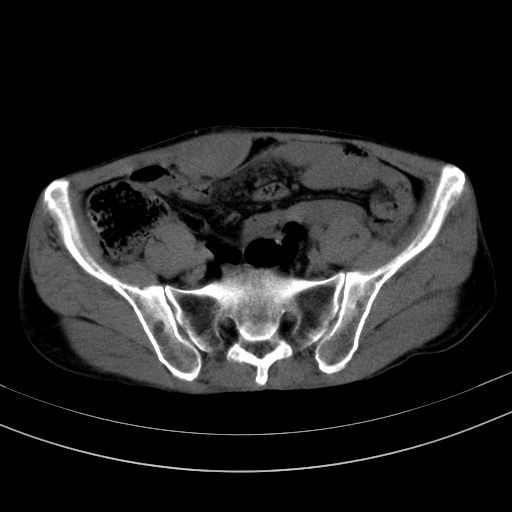

以下是引用37度在2010-1-9 14:37:00的发言:[br]1.双肾囊肿,左肾积水结石,.胆总管轻度扩张;[br]2.病灶在腹膜外,考虑纤维瘤。

以下是引用dyqct在2010-1-9 17:56:00的发言:[br]考虑:1.双肾囊肿,左肾积水结石、旋转不良。[br] 2.右侧腹直肌血肿或纤维瘤。[br]肠道准备不好。做个增强。